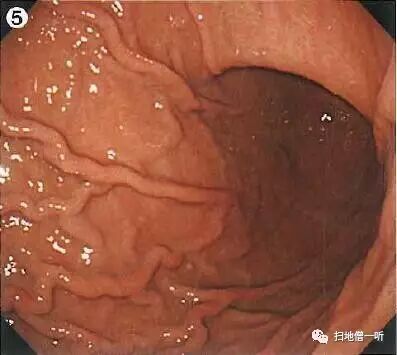

背景粘膜无萎缩表现,RAC可见,提示HP未感染。此情况分化癌不多见,警惕未分化癌特别是印戒细胞癌的发生。此病例胃角大弯远景观察下可见一小片状褪色粘膜。

此区域内镜在行进插入幽门十二指肠过程中可能出现压擦,如病变较小IIb型褪色病变,则非常难以发现。故建议此部分病变应在进镜前观察,必要时活检。

靛胭脂染色后边界不清,表面无凸凹变化。